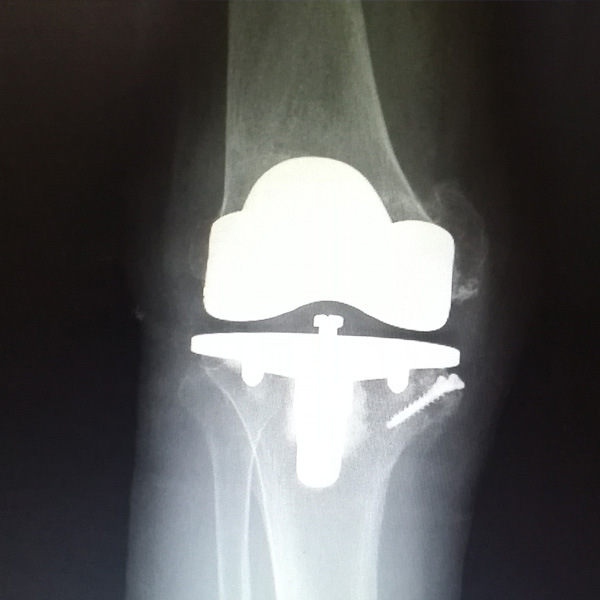

膝關(guān)節(jié)內(nèi)翻

患者劉某某,女66歲,左側(cè)膝關(guān)節(jié)嚴重內(nèi)翻(俗稱的“羅圈腿”),疼痛到不能生活自理。經(jīng)平臺推薦到哈爾濱醫(yī)科大學(xué)附屬第二醫(yī)院骨關(guān)節(jié)科就診,......